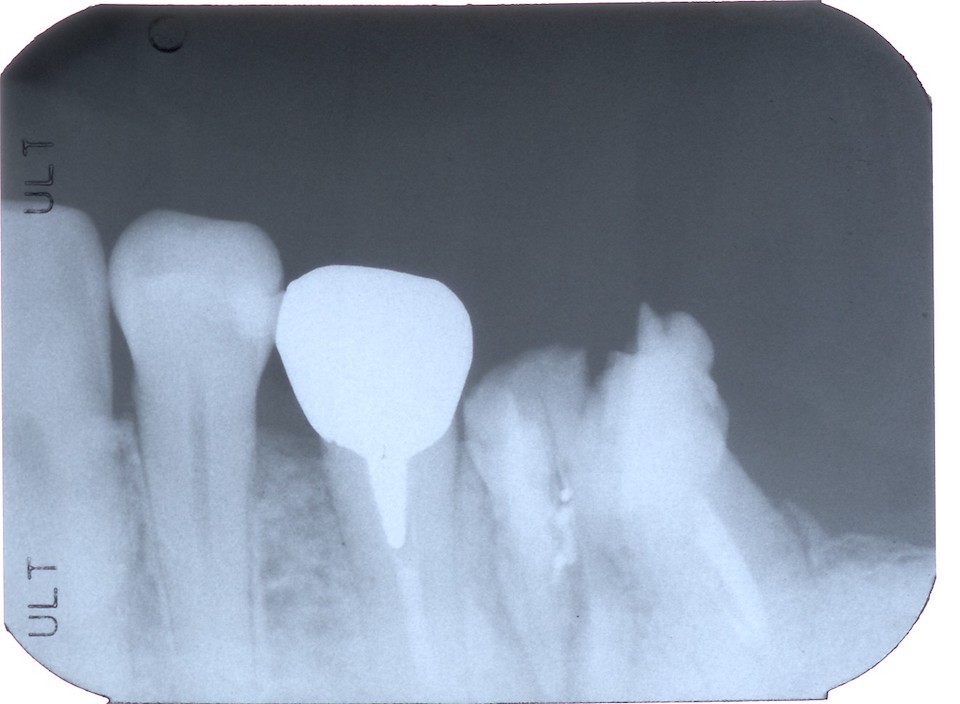

今日の抜歯再植術シリーズ39.1 2025.11.14

今日の抜歯再植術シリーズ39.0 2025.11.13

今日の抜歯再植術シリーズ38.3 2025.10.14